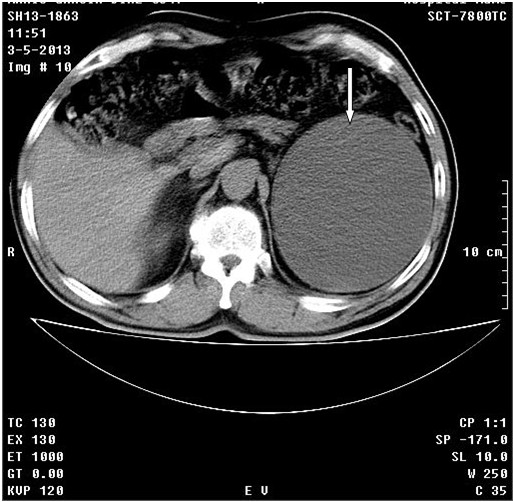

Se realizó tomografía axial computadorizada simple y TAC simple y tomografía con contraste endovenoso y con vistas tardías. Se observó el riñón derecho con dilatación moderada del sistema excretor con posibilidad de quiste asociado (Flecha fina). En el riñón izquierdo se observó proceso expansivo de baja densidad de 13 cm con gruesa cápsula hacia la porción superior del mismo con componente quístico asociado, que provoca retardo en la eliminación del contraste por este lado. (Figuras 1 A, B, C, D flechas gruesas)

Tumor en riñón izquierdo, carcinoma papilar acinoso de 10 cm de células renales. Al paciente se le realizó una cirugía polar de RI, evolucionó satisfactoriamente.